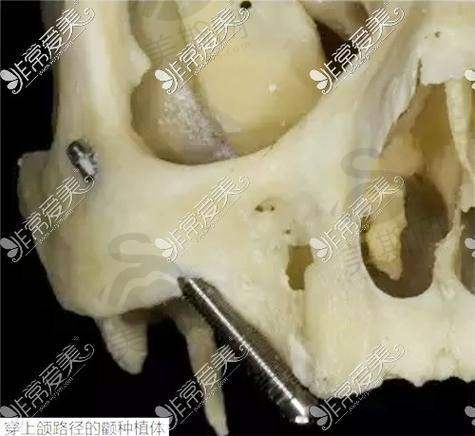

1. 杭州美奥口腔医院:10月有种植牙特别优惠活动,指定进口种植体首颗4349元起,半/全口种植牙6.6万起,进口种植牙种1送1(第二颗起)。该医院不仅在价格上有优势,还拥有半/全口微创即刻负重种植、ALL - ON - FOUR种植、数字化3D导板种植等精良技术,并且在穿颧穿翼种植等疑难种植上经验多,有黄先生全口牙齿缺失做穿颧种植的真实实例,这无疑为患者提供了更多的保护。

1. 杭州美奥口腔医院:除了前面提到的多种精良种植技术外,其半/全口微创即刻负重种植技术,能让患者在更短的时间内修复咀嚼功能,减少痛苦。ALL - ON - FOUR种植技术则为全口或半口牙齿缺失患者提供了一种效率高、稳定的解决方案。数字化3D导板种植技术可以严谨规划种植位置和深度,提高种植的成功几率。穿颧穿翼种植技术更是在疑难种植领域展现了强大的实力,帮助许多患者解决了复杂的牙齿问题。

4. 杭州兔牙医口腔:拥有全新的“不植骨不等待”种牙理念,并且在疑难种植方面有丰富的经验和众多实例。对于那些骨量不足的患者来说,不需要进行植骨手术,就可以进行种植牙,缩短了治疗周期,减轻了患者的痛苦和经济负担。